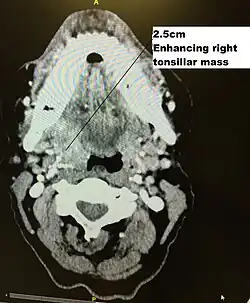

Initial diagnosis requires visualisation of the tumour either through the mouth or endoscopically through the nose using a rhinoscope, illustrated to the right, followed by biopsy.

Staging is generally by the UICC/AJCC TNM (Tumour, Nodes, Metastases) system.[68] Staging is based on clinical examination, diagnostic imaging, and pathology. On imaging, involved lymph nodes may appear cystic, a characteristic of HPV+OPC.[69]